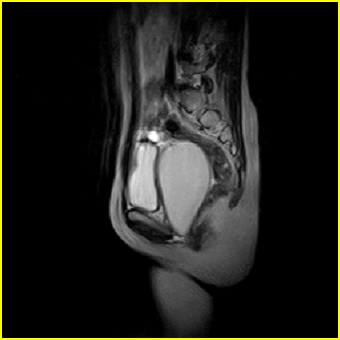

女、15岁、下腹疼痛2天,排尿困难1天。查体:处女膜闭锁,距处女膜约4至5cm处扪及一约5cm直径的圆形包块,张力较高,触痛明显、欠活动。b超提示子宫增大伴宫内增强回声团。

影像意见:子宫直肠陷凹积血。

更正影像意见:阴道积血。

处女膜闭锁,阴道积血

处女膜闭锁,阴道积血,子宫积血.

先天性处女膜闭锁,伴阴道积血,不除外先天性阴道粘液囊肿形成。

阴道积血,子宫积血.

子宫及阴道积血。

处女膜闭锁,伴子宫及阴道积血.